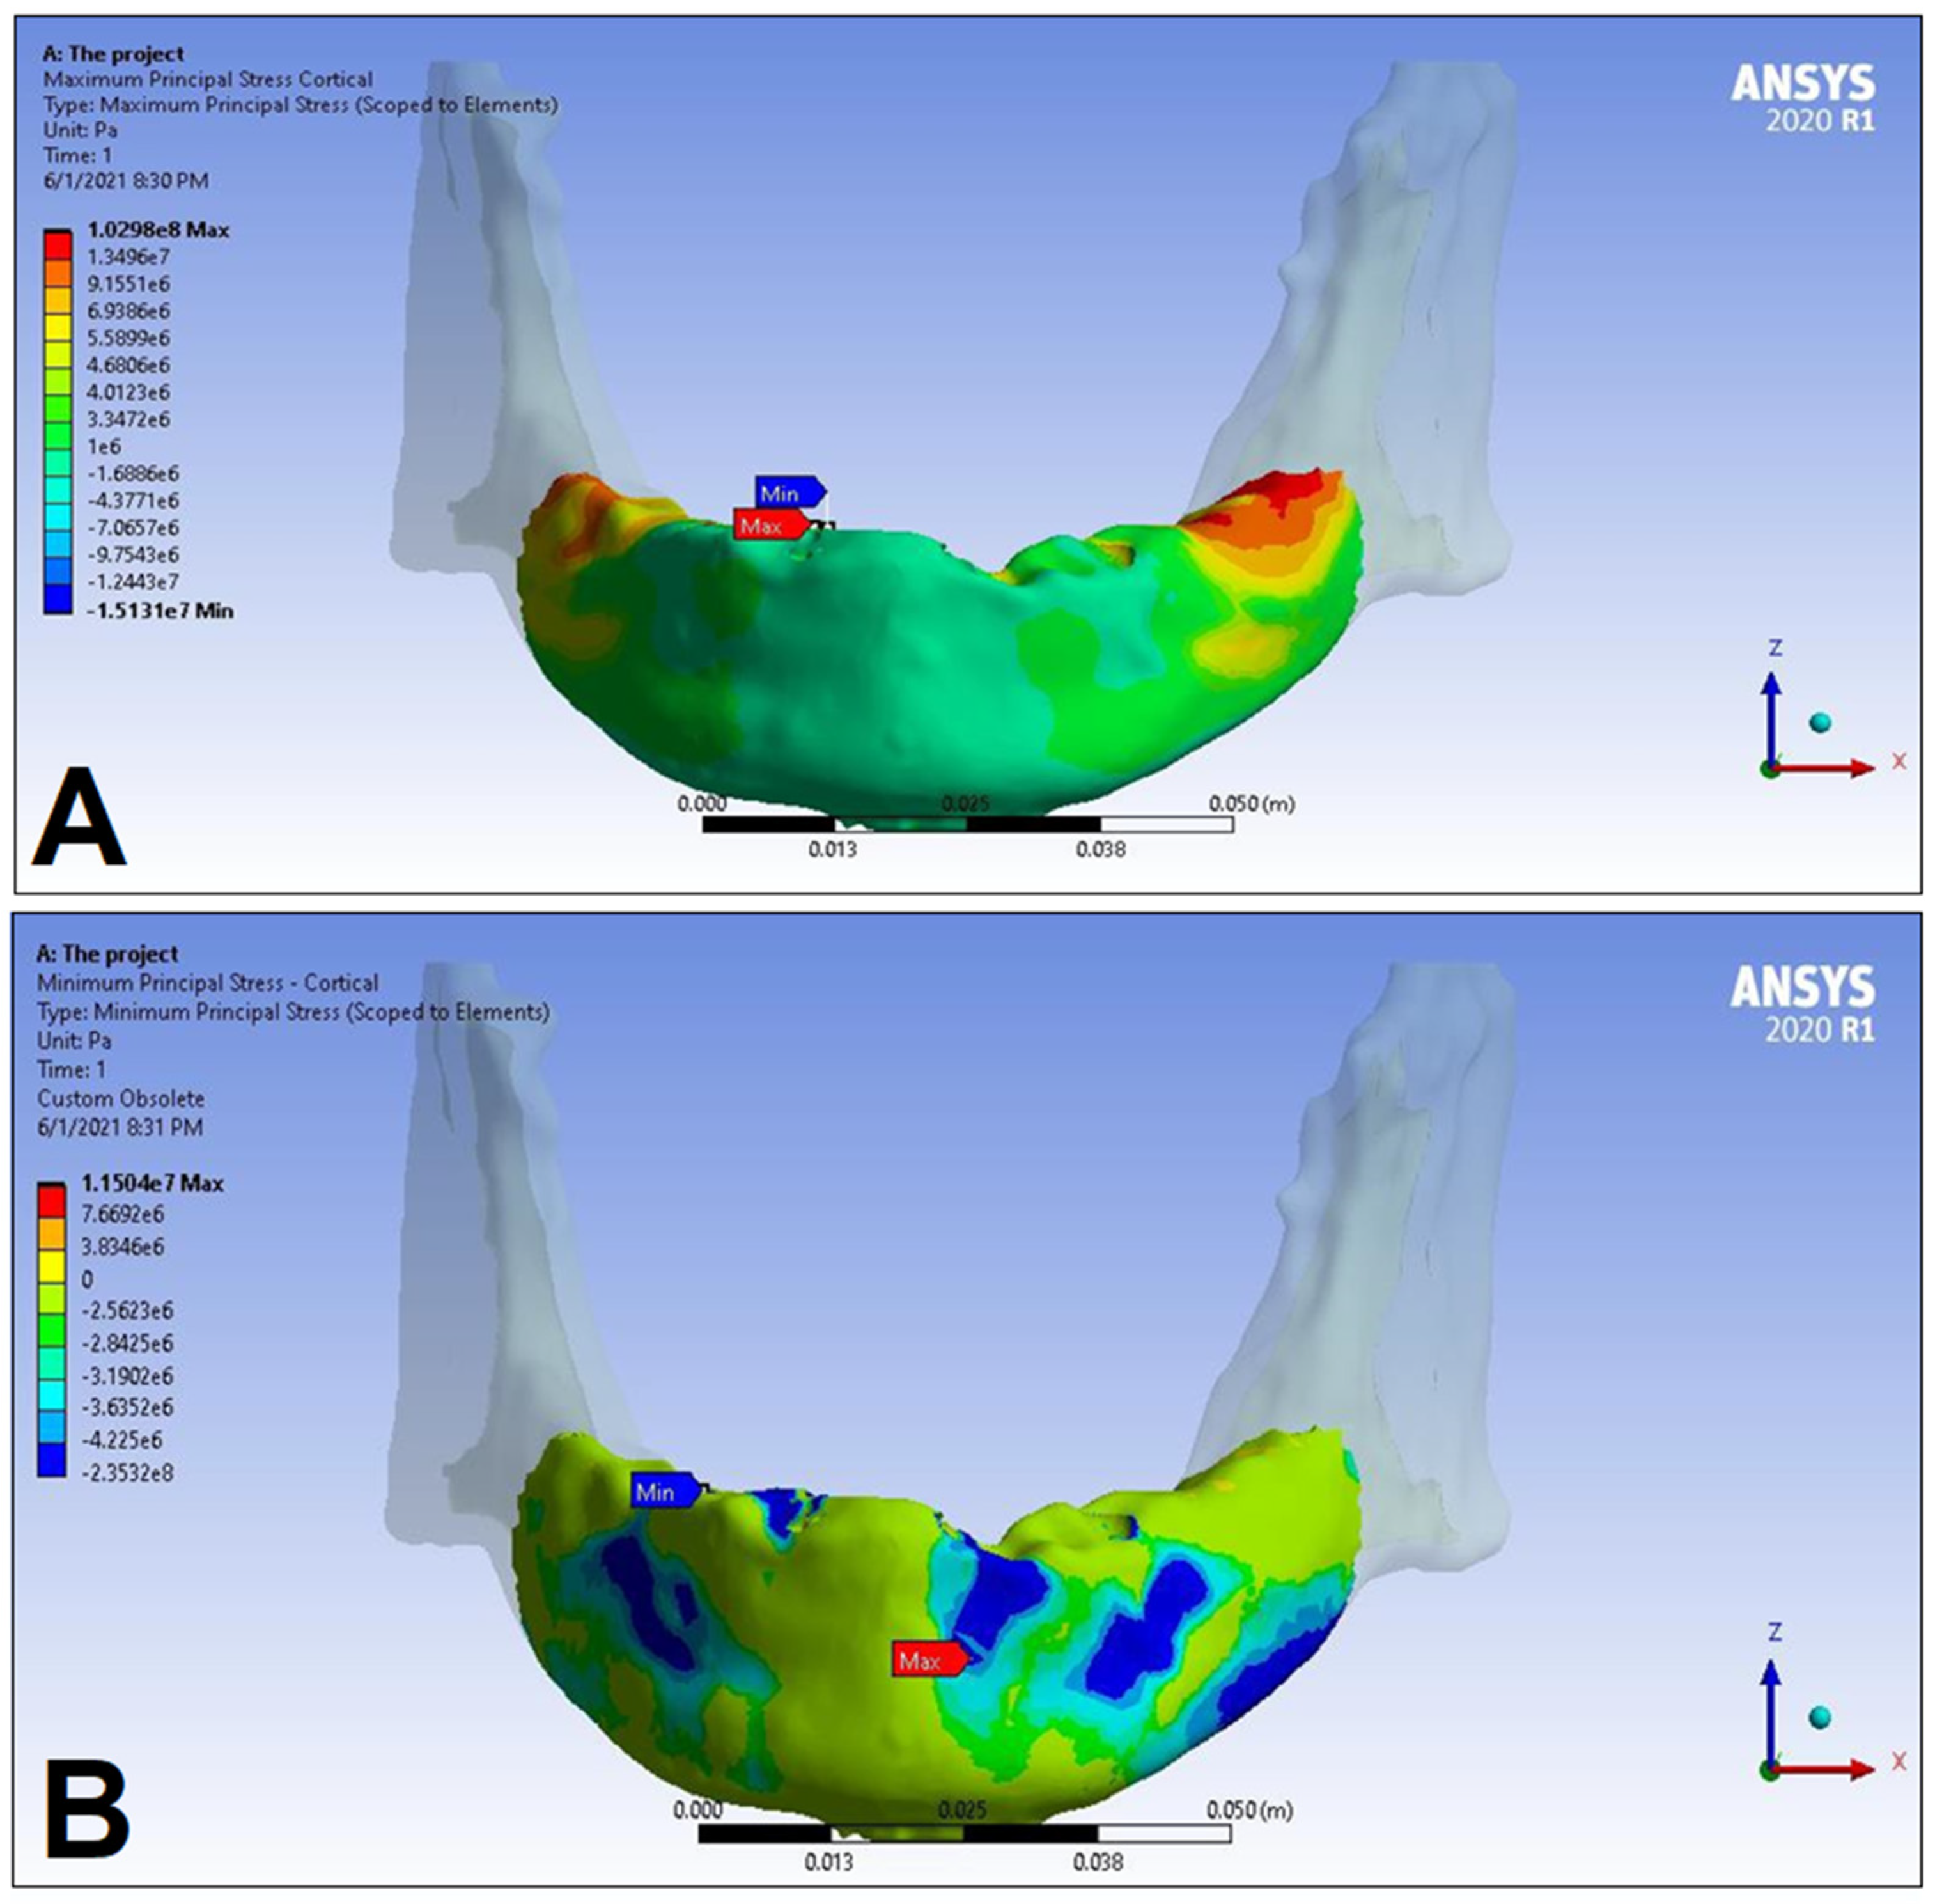

3. Results

| LC1 | LC2 | LC3 | LC4 | ||||||

|---|---|---|---|---|---|---|---|---|---|

| S1 | S2 | S1 | S2 | S1 | S2 | S1 | S2 | ||

| Cortical bone | Pmax [MPa] | 76.39 | 88.51 | 89.57 | 102.98 | 85.63 | 95.48 | 81.02 | 93.15 |

| Pmin [MPa] | −115.30 | −222.76 | −136.4 | −265.35 | −172.30 | −252.61 | −125.20 | −235.32 | |

| Trabecular bone | Pmax [MPa] | 2.49 | 2.24 | 3.03 | 2.62 | 2.95 | 2.52 | 2.92 | 2.59 |

| Pmin [MPa] | −2.81 | −2.89 | −3.34 | −3.38 | −3.25 | −3.25 | −3.49 | −3.52 | |

| Peqv [MPa] | 166.40 | 244.92 | 166.36 | 279.69 | 164.36 | 265.58 | 142.27 | 260.77 | |